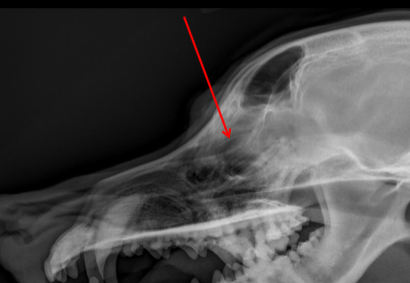

ID Radiographic View

Lateral

Frontal Sinus

ID

Zygomatic Arch

Tympanic Bulla

ID.

Horizontal Ear Canal

Occipital Condyles

Temporomandibular Joint